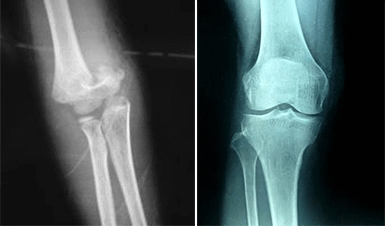

(图:膝关节刚出现红肿时的照片)

(图:于老师膝关节治疗前后对比)

经过两个疗程的治疗以后,于老师感觉效果特别明显,膝盖红肿疼痛基本消失,膝关节也可以自由弯曲了,复查显示已经达到临床 的标准。